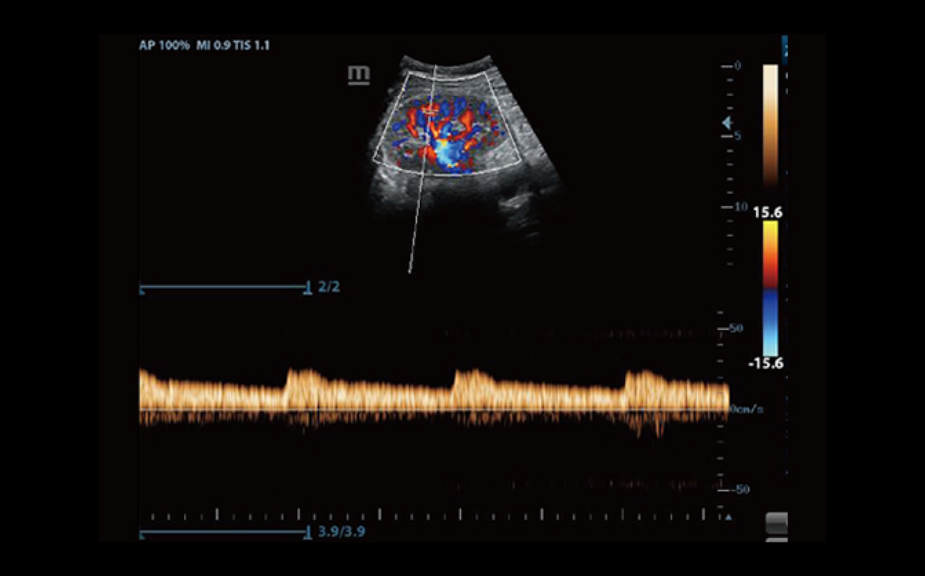

IMT (Intima-Media Thickness)

Automatyczny pomiar grubo?ci kompleksu Intima-Media na przedniej i tylnej ?cianie naczynia, umo?liwia precyzyjn? ocen? stanu t?tnicy szyjnej.

iTouch?

Uzyskanie natychmiastowej, automatycznej optymalizacji obrazu w trybie B i PW, po naci?ni?ciu jednego klawisza.